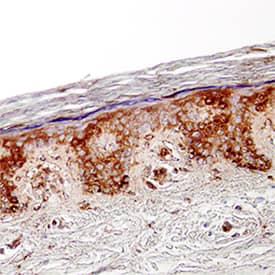

CCL27/CTACK antibody in Human Skin by Immunohistochemistry (IHC-P).

CCL27/CTACK in Human Skin.

CCL27/CTACK was detected in immersion fixed paraffin-embedded sections of human skin using Mouse Anti-Human CCL27/CTACK Monoclonal Antibody (Catalog # MAB376) at 25 µg/mL overnight at 4 °C. Tissue was stained using the Anti-Mouse HRP-DAB Cell & Tissue Staining Kit (brown; Catalog # CTS002) and counterstained with hematoxylin (blue). Specific staining was localized to cytoplasm in keratinocytes. View our protocol for Chromogenic IHC Staining of Paraffin-embedded Tissue Sections.